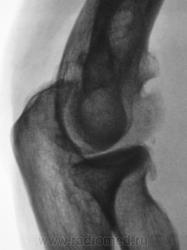

Пациент направлен на рентгенографию локтевого сустава. Была травма или не была не помнит. Пациент весьма пьющий, направлен хирургом с диагнозом "перелом". Рука в локтевом суставе полность не разгибается.

Ваше мнение уважаемые коллеги?

Наверно, застарелый перелом в области блока плечевой кости. Не понятен периостит.